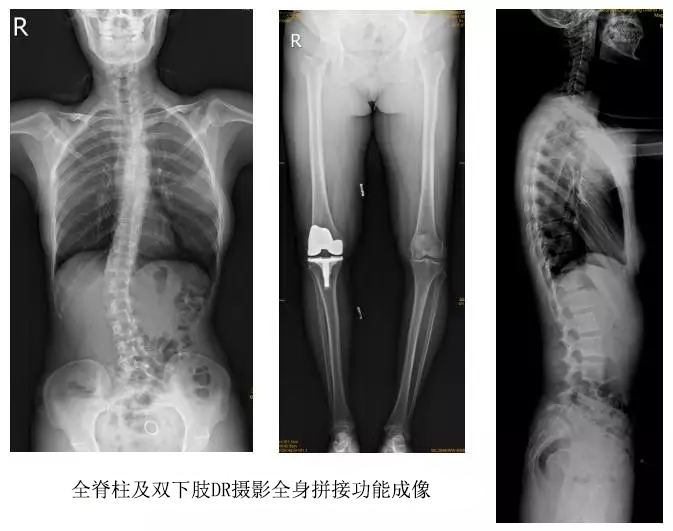

以某院所攝X光片為例,對比傳統(tǒng)攝片與全身拼接功能的區(qū)別:

傳統(tǒng)X光片只能觀察每個部位的局部情況,無法在統(tǒng)一體上進行連續(xù)、全面的觀察,全脊柱及下肢全長片則能直觀的看到整體形變。通過DR全身拼接功能實現(xiàn)的完整成像,為診治脊柱及下肢畸形提供了完美的臨床影像依據(jù),對臨床診斷、術前手術方案的制定和術后療效的評估等臨床應用具有十分重要的意義,有效滿足了此類疾病臨床診斷和治療的要求。

通過以上對比,可以發(fā)現(xiàn),在缺少DR全身拼接功能的條件下,傳統(tǒng)X光攝片無法有效解決骨科常見疾病如脊柱側彎及下肢畸形的臨床診斷。在國家大力推進健康中國、人民不斷增長的醫(yī)療需求的大背景下,醫(yī)療缺陷將不斷被合理技術替代,因此從對立面評測,如今,沒有全身拼接功能的DR就不是合格的DR。